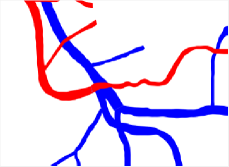

In this paper, we propose a coherence-penalized minimal path model, where the associated minimal paths favour to pass by a vessel that is located in the flatten region of an external feature map. We observe that along a piece of retinal vessel, the values of gray levels vary slowly. More specifically, retinal arteries have lower contrast of gray levels than veins due to the blood materials and imaging modality. In other words, in some extent the arteries and veins are distinguishable in terms of vesselness values. Such an observation can be used to solve the short branches problem that the minimal paths associated to a metric may pass through segments belonging to different vessels as shown in Figs. 1b and 1c. Fig. 1d shows the result from the proposed method, which can avoid such problem. Fig. 1a gives the artery-vein (AV) groundtruth. In this paper, we denote by blue and green dots the source and end points respectively.

Validation. We validate our minimal path model on respective 54 and 30 patches obtained from the DRIVE [14, 15] and the IOSTAR [16] datasets with AV groundtruth. Each artery involved in these parches locates near a vein or crossing it at least once. Our goal is to extract the artery between two given points. In order to get the quantitative evaluation, we first convert each continuous spatial path to an 4-connected digital path which is considered as a pixel collection. We denote by the collection of digital path pixels inside the artery groundtruth map . Thus, a measure can be simply defined as , where and mean the respective number of elements involved in and . We compare our model to four existing minimal path models: the isotropic Riemannian (IR) model [1], the anisotropic radius-lifted Riemannian (ArR) model [4], the isotropic orientation-lifted Riemannian (IoR) model [5] and the curvature-penalized (CuP) model [7]. The construction of these metrics are based on the OOF outputs [12]. Note that a centerline-based potential is chosen so that we remove the radius dimension of [5] to reduce computation complexity. The results in terms of the score are presented in Table 1, including the average (Avg.), maximum (Max.), minimum (Min.) and standard deviation (Std.) values. In both DRIVE and IOSTAR datasets, our method can achieve the best performances thanks to the coherence penalization. Note that in Table 1, we evaluate our method by using the refined paths instead of using the original coherence-penalized minimal paths. For comparisons in visualization, we show the minimal paths from the ArR metric , the CuP metric and the proposed coherence-penalized metric on three retinal patches as shown in Fig. 3. The targeted artery vessels which cross veins at least once are labeled by red color in column 1. The paths shown in column 4 from the proposed metric are results after refinement. One can claim that our method indeed can catch expected arteries while other metrics fall into the traps of short branches combination.